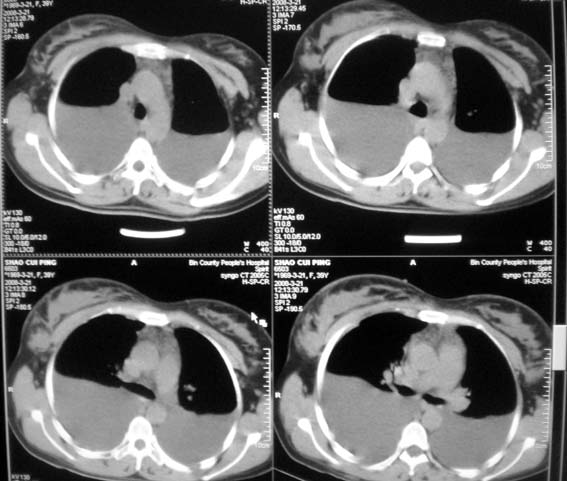

以下是引用zsl6918在2008-3-21 21:41:00的发言:[br]胸腔积液,心包积液,明确性质有难度。常规思路考虑结核性,建议抽液化验明确。

以下是引用随光逐影在2008-3-21 23:13:00的发言:[br]1)右肺中叶及左肺上叶舌段感染性病变。2)右肺中叶周围型肺癌待排。3)双侧胸腔积液并双下肺部分肺组织膨胀不全。4)心包积液。

以下是引用拾荒者在2008-3-22 21:21:00的发言:[br]胸腔积液、心包积液,双下肺膨胀不全,建议穿刺细胞学检查或抽液后进一步ct检查。